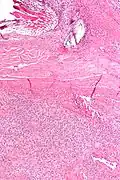

Micrograph of a solitary fibrous tumor. H&E stain.